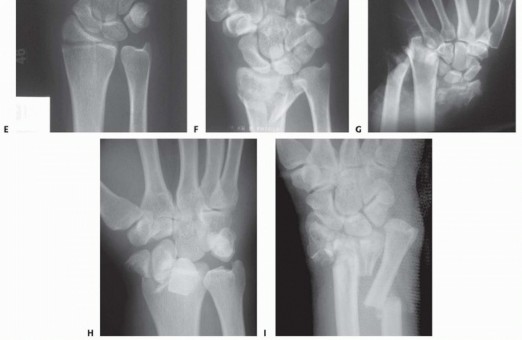

### FIG 3 • Pathogenesis of dorsal radius fractures. A. Dorsal bending. B. Volar bending. C. Dorsal shear. D. Volar shear. E. Radial shear. F. Three-part articular. G. Comminuted articular. H. Carpal avulsion. I. High energy. 78 Dorsal shearing injuries present as fractures of the dorsal rim and are often associated with dorsal instability of the carpus ( FIG 3C). These injuries often have a depressed articular fragment and may have additional radial column involvement. Volar shearing injuries present as displaced fractures of the volar rim and result in volar instability of the carpus ( FIG 3D). This pattern often has multiple articular fragments and is highly unstable. It is not usually amenable to closed methods of treatment. Radial shearing fractures (chauffeur's fracture) are identified by a characteristic transverse fracture line across the radial styloid that extends into the radiocarpal joint. These injuries often have more extensive chondral disruption than may be appreciated from the radiographic findings ( FIG 3E). Simple three-part fractures are usually the result of lowenergy injuries that combine a dorsal bending mechanism with some axial loading across the carpus ( FIG 3F). This pattern is characterized by the presence of an ulnar corner fragment involving the dorsal portion of the sigmoid notch, a main articular fragment, and a proximal shaft fragment. Complex articular fractures are usually the result of axial loading injuries from moderate to high-energy trauma. In addition to articular comminution, this pattern may often generate a significant defect in the metaphyseal cavity or complete disruption of the DRUJ ( FIG 3G). The avulsion/carpal instability pattern is primarily a ligamentous injury of the carpus with associated osseous avulsions of the distal radius. Bone fragments are typically small and very distal ( FIG 3H).